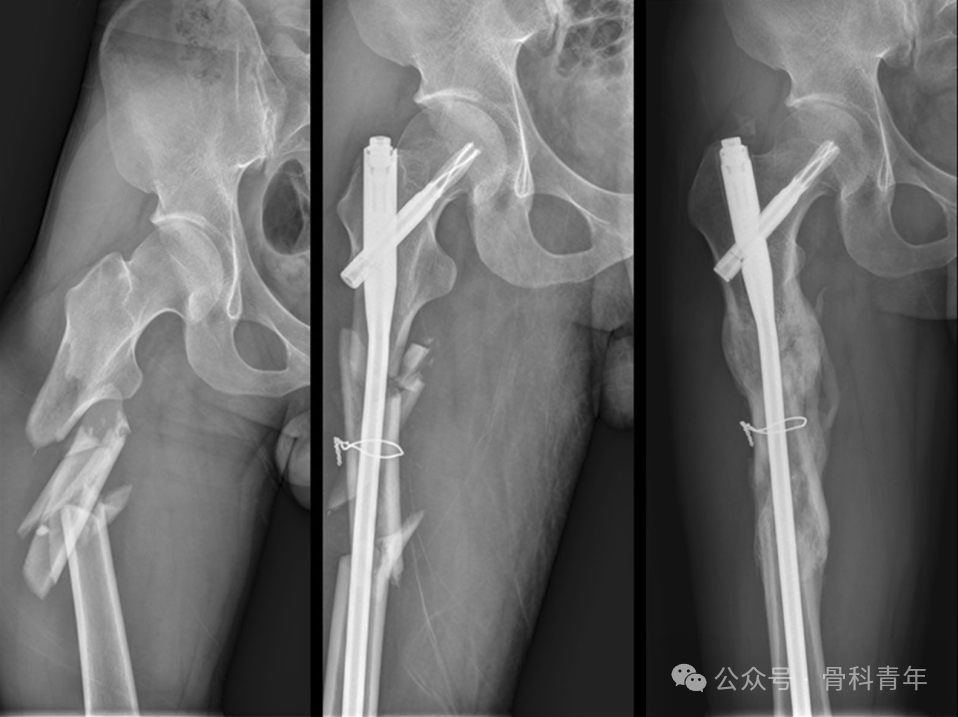

股骨干骨折

文章纳入了37例粉碎性股骨干骨折病例,16例行钢丝环扎辅助固定,21例行单纯髓内钉固定:

文章结果表明,钢丝环扎组,在骨科愈合时间,术后12月和24月HSS评分、HHS评分,骨折愈合率上均存在明显优势。建议对粉碎性股骨干骨折行钢丝环扎辅助固定。

在另一篇对股骨干粉碎性骨折钢丝环扎的固定研究中,尽管在骨折愈合率和并发症上未发现统计学差异,但钢丝组骨折复位较非钢丝辅助复位组好,且并不增加并发症风险。钢丝环扎具有非劣效应。